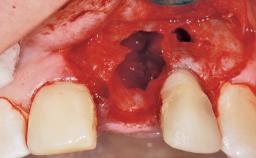

This 43-year-old male patient, a non-smoker, came to our practice because of a fracture of tooth 12 caused by a bicycle accident. Due to the combined para- and infrabony crown and root fracture, tooth extraction, and subsequent implant placement were suggested to the patient as the therapy of choice. The patient had high esthetic expectations with regard to the treatment outcome and asked for an immediate fixed provisional restoration. His individual esthetic risk profile summed up to a medium esthetic risk.